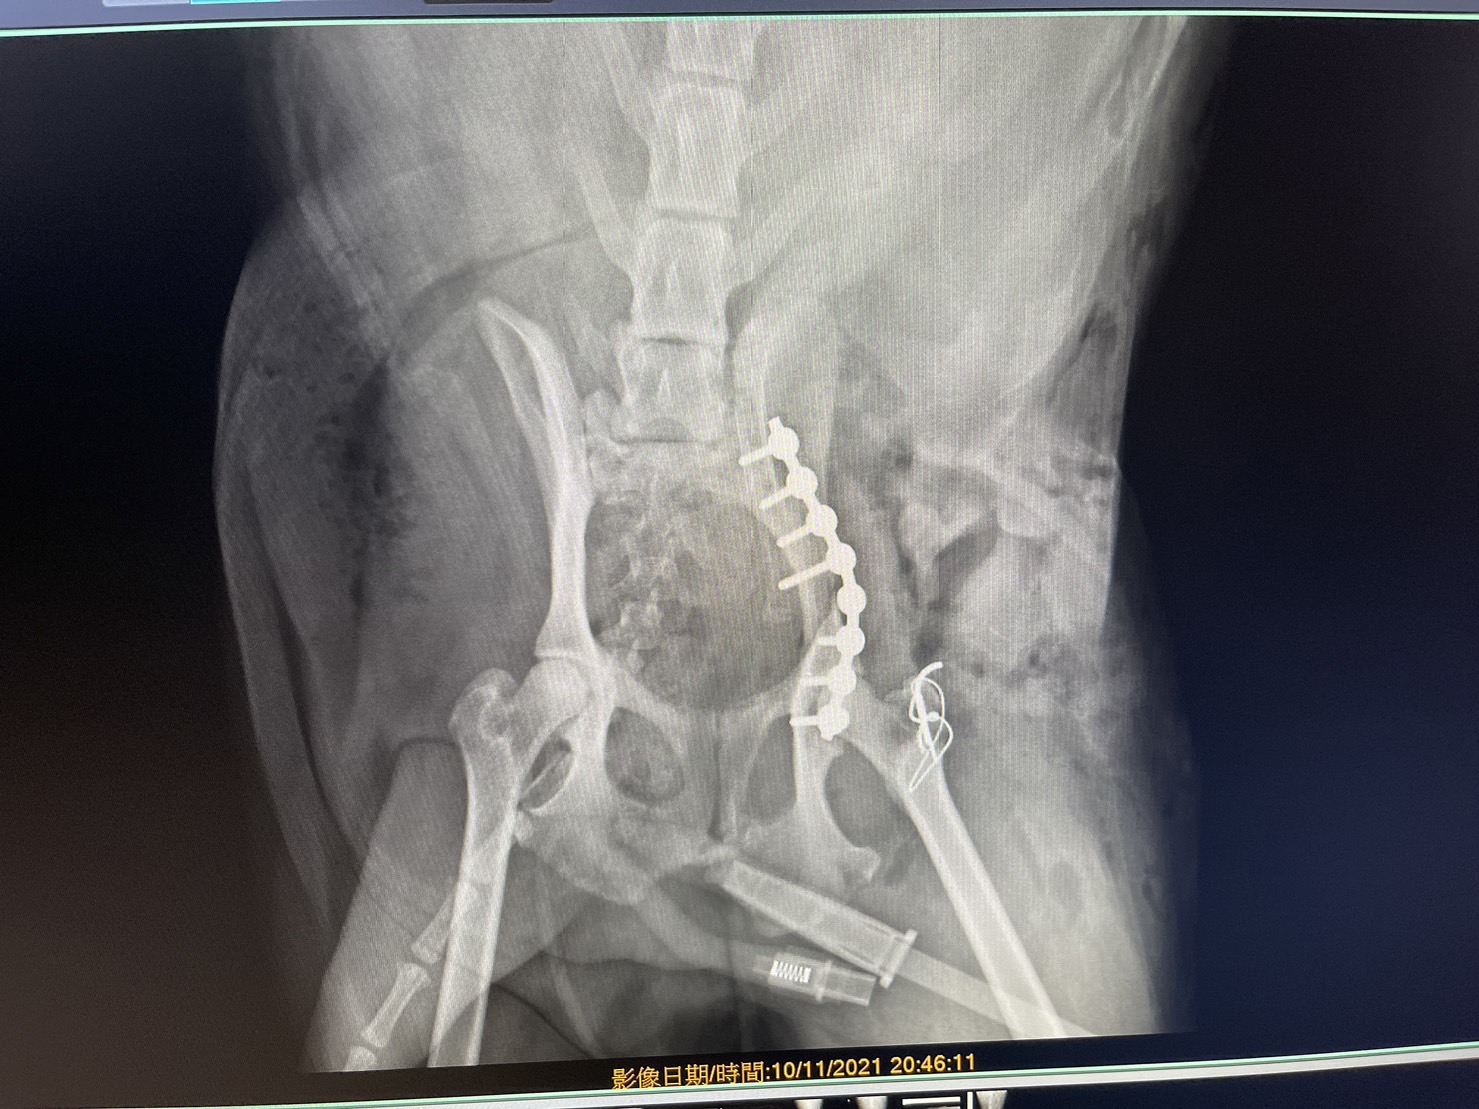

狗狗電腦斷層掃描 不明原因口腔出血 嚴重牙周病 口腔惡性腫瘤 鱗狀上皮細胞癌(Squamous cell carcinoma,SCC)

主訴嘴巴突然流血 口腔潰爛 左下顎腫脹 同時有嚴重牙周病 經由口腔採樣 電腦斷層掃描 確認為鱗狀上皮細胞癌(Squamous cell carcinoma,SCC)同時已經侵犯下顎骨。確診後經由外科醫師、腫瘤科醫師、電腦斷層影像科醫師共同擬定治療計畫後

,大範圍切除左下顎,經過一年追蹤,目前狗狗一切安好喔。

*康復後

*電腦斷層影像